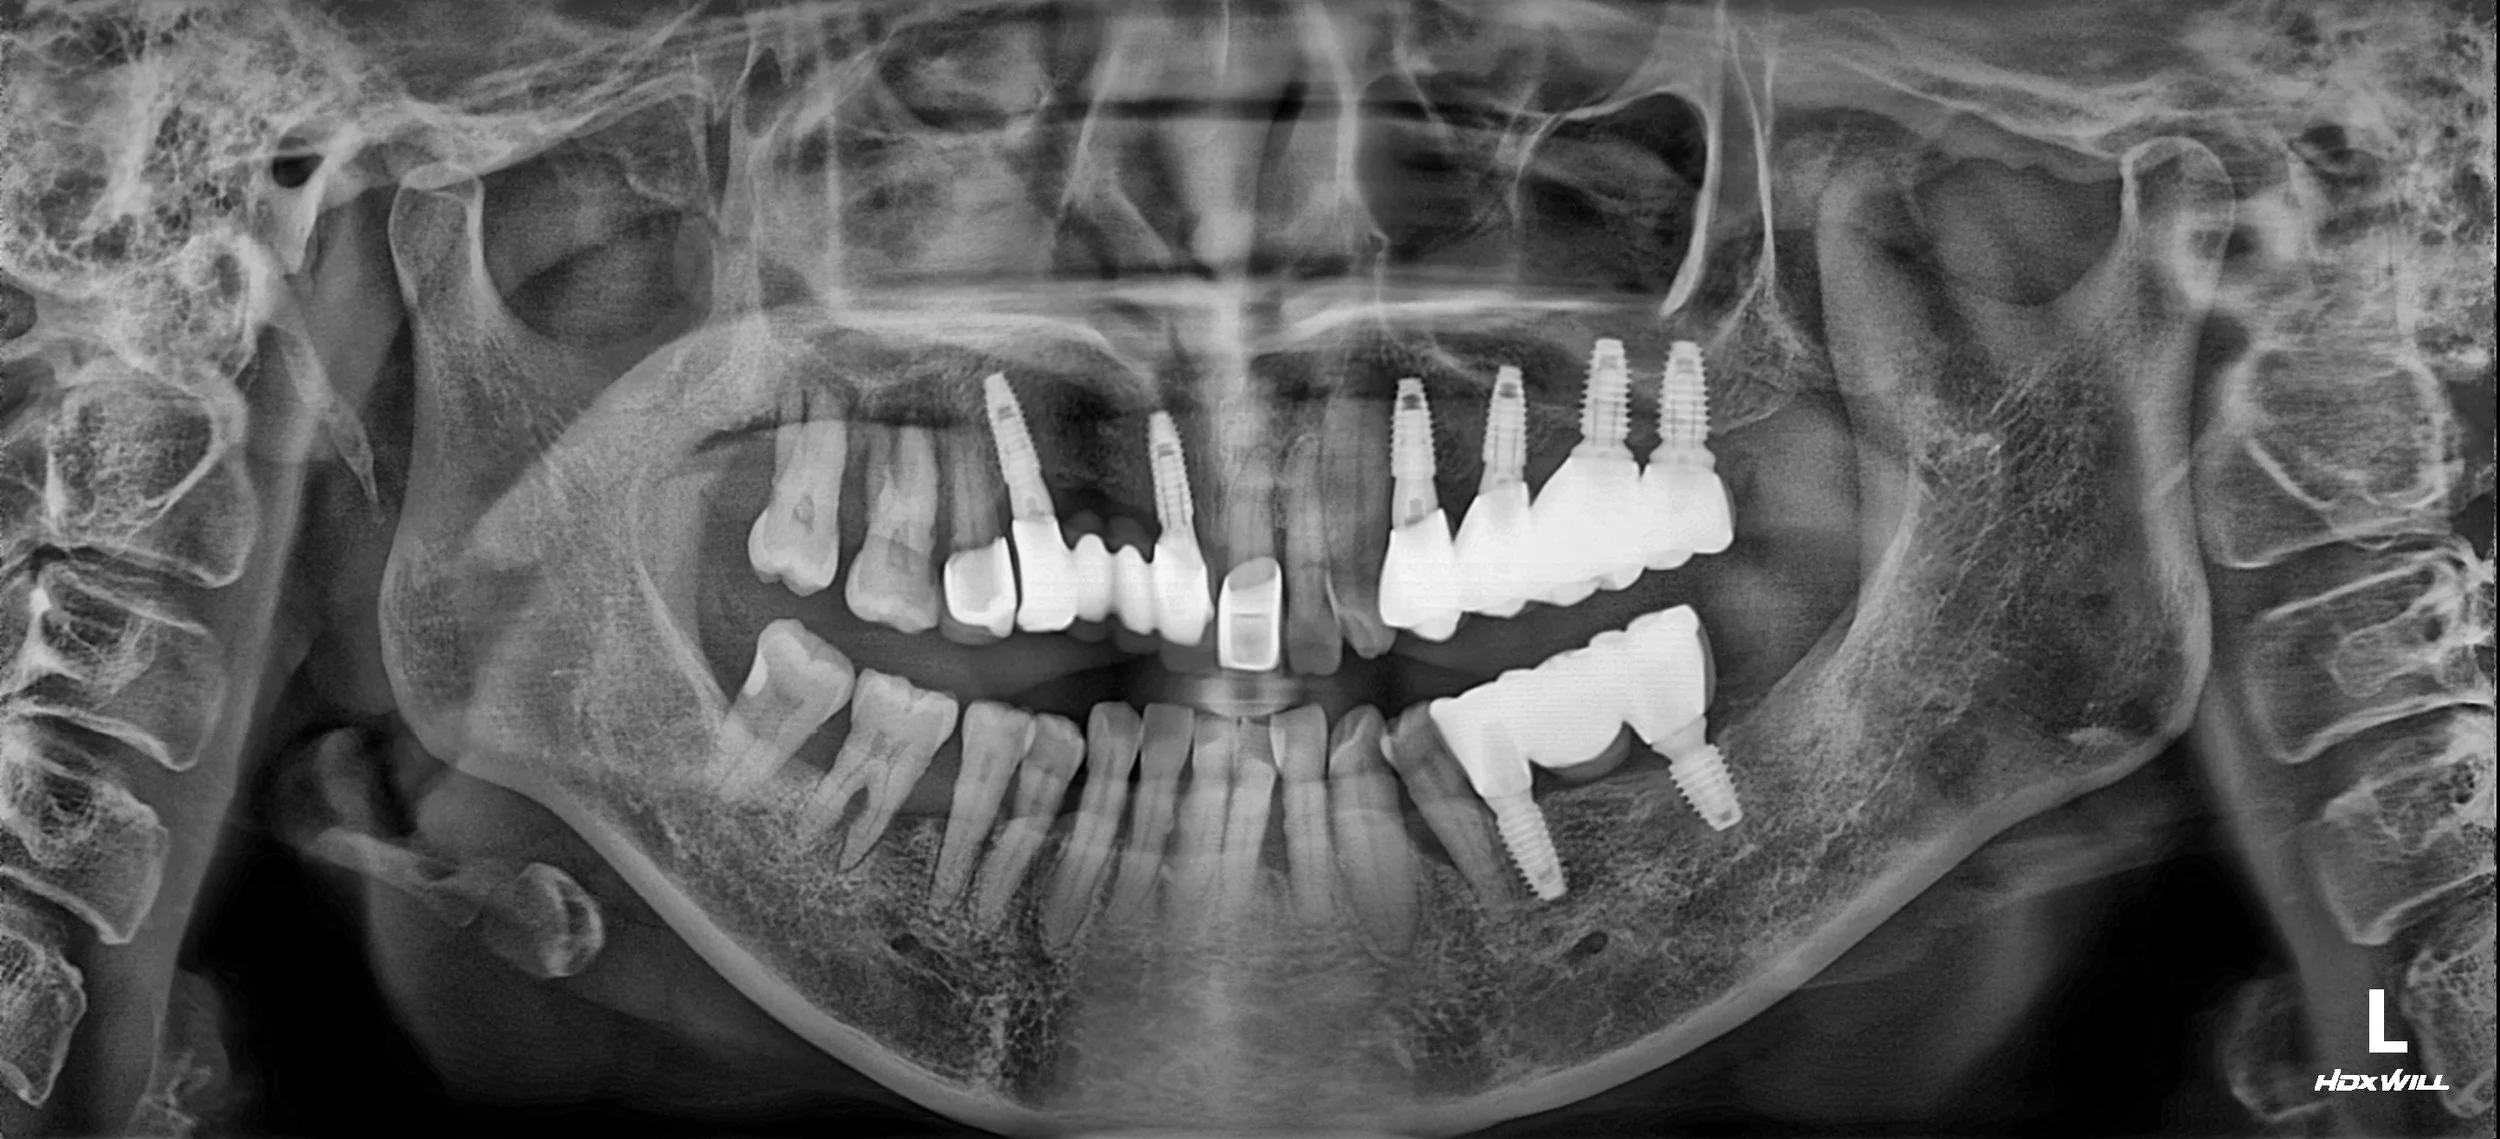

OPG - BEFORE

• Severe Alveolar Resorption: Chronic pressure from the dentures had led to extreme horizontal and vertical bone loss, particularly in the edentulous spans.

• Total Occlusal Collapse: The lack of stable posterior stops had compromised the patient's vertical dimension and chewing capacity.

• Patient Preference for Phased Care: The patient requested a sequential approach to treatment, prioritizing the most urgent edentulous areas while deferring treatment for quadrants 10 and 40.